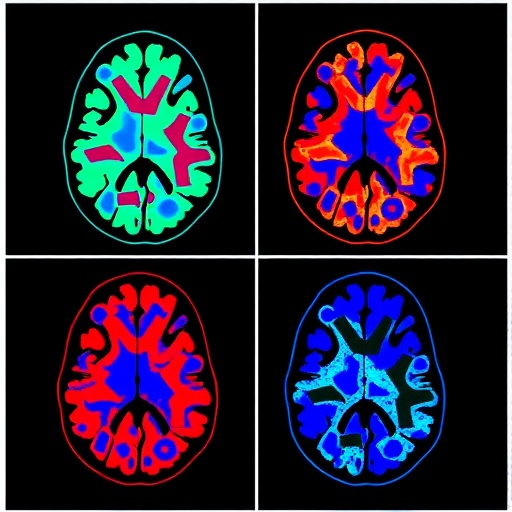

The integration of imaging techniques with omics is particularly promising. Imaging technologies such as MRI and PET scans allow researchers to visualize structural and functional changes in the brain, offering insights into neuronal degeneration and amyloid deposition. Meanwhile, omics technology facilitates a comprehensive analysis at molecular levels, revealing biochemical alterations that can signal disease pathology. This dual approach seeks to unravel the complexities of Alzheimer’s disease, enabling clinicians to develop a multifaceted diagnostic framework that surpasses conventional methods.